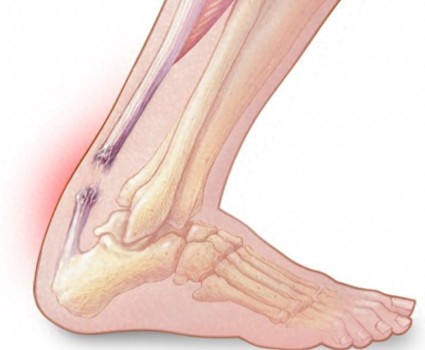

曝司機(jī)騷擾未成年女乘客問是不是處女 惡劣行為引發(fā)公憤 醫(yī)學(xué)專家:塔圖姆可能是跟腱撕裂 傷情嚴(yán)重需長(zhǎng)期恢復(fù)

醫(yī)學(xué)專家:塔圖姆可能是跟腱撕裂 傷情嚴(yán)重需長(zhǎng)期恢復(fù) 35歲女子長(zhǎng)期不吃早餐主食查出兩種癌癥 提醒年輕人:按時(shí)吃飯,少熬夜